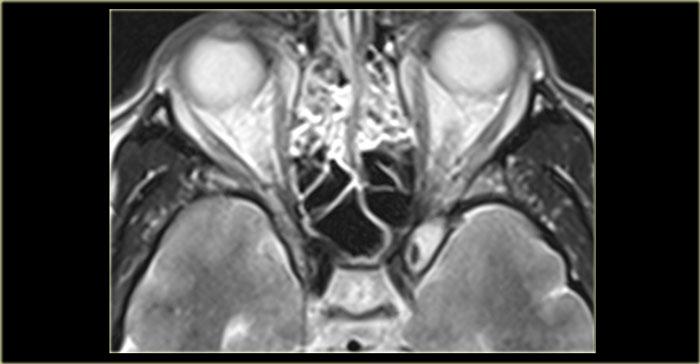

Viêm Mô Tế Bào Hốc Mắt và Áp Xe

Bên trái là chuỗi xung T1W mặt phẳng axial, bên phải là chuỗi xung T2W mặt phẳng coronal.

Có bất thường ở bên trái, nhưng ở mức độ ít hơn cũng có ở bên phải.

Hãy cố gắng xác định các cấu trúc nào bị tổn thương.

Các mũi tên vàng chỉ vào ống lệ mũi.

Túi lệ kết nối với ống lệ, sau đó dẫn lưu vào ngách mũi dưới.

Bên trái có phù nề mô mềm quanh hốc mắt trước vách ngăn.

Trên hình ảnh coronal, có tín hiệu cao hai bên tại vị trí nối giữa ống lệ mũi và túi lệ, gợi ý ổ dịch.

Bên trái cũng có phù nề mô xung quanh.

Chuỗi xung T1W sau tiêm thuốc tương phản từ, mặt phẳng axial và coronal.

Ở phía ngoài ống lệ mũi hai bên, có các ổ dịch hiện nay cho thấy hình ảnh ngấm thuốc ngoại vi.

Các hình ảnh bổ sung (chuỗi xung T2W) cho thấy bệnh lý niêm mạc xoang hàm phải và mức dịch trong xoang hàm trái, ngoài ra còn có bệnh lý xoang sàng và xoang bướm lan rộng.

Bệnh nhân này bị viêm xoang cấp tính có biến chứng viêm mô tế bào hốc mắt và viêm túi lệ kèm áp xe.

Hẹp ống lệ mũi do bẩm sinh hoặc do viêm là yếu tố nguy cơ dẫn đến viêm túi lệ.